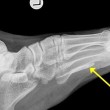

Jonathan Darby, medico specializzato in infezioni, ha notato dalle radiografie due pezzi di verme della Guinea, uno nel piede e uno alla caviglia. Questo verme, ha spiegato il medico, è un parassita che si annida generalmente nell’intestino, dove deposita le sue larve. Un processo che può richiedere anni, spiega il medico:

“Il parassita può sopravvivere nel corpo umano per anni oppure morire, decomponendosi e causando problemi e infezioni come accaduto per il nostro paziente”.